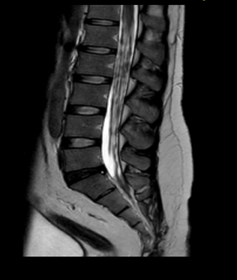

Se solicitó inicialmente Imagen de resonancia magnética (IRM) de columna lumbosacra simple y estudios de neurofisiología. La electromiografía más neuroconducciones de las 4 extremidades reportó neuropatía mielínica de expresión leve del nervio peroneo motor. Imagen de resonancia magnética lumbosacra simple muestra hallazgos compatibles con aracnoiditis adhesiva (figura 1). Ante estos hallazgos, se complementan estudios con resonancia torácica y cerebral con contraste. En la resonancia de columna torácica, se observa incipiente siringomielia (figura 2.) y la resonancia cerebral con contraste no mostró alteraciones.

Figura 2

A nivel T10-T11 se identifica una lesión focal ovoide de contornos claramente definidos, de aproximadamente 10 mm de diámetro mayor, en el plano craneocaudal, de localización central en el cordón medular, hiperintensa en las imágenes. Incipiente siringomielia y alteración en la dinámica del líquido cefalorraquideo.